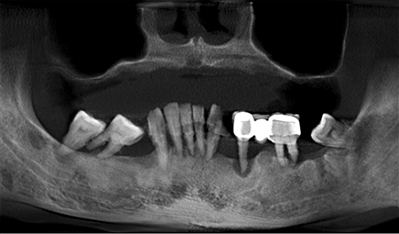

吴伯使用活动假牙快20年了,但最近经常牙龈肿痛,好不容易戴上去的假牙,没吃两口饭又松脱了。听说种植牙稳固有力,吴伯便萌生了种牙的想法。经检查,吴伯牙床条件已不再适合佩戴假牙,且牙槽骨已经严重萎缩。假牙用不了,种牙难度大,正愁怎么办的吴伯来到了柏德口腔。

兰院长给出的种牙方案是,在植骨同时植入5颗种植体,支撑半口牙桥完成修复。这样设计能使骨生长与骨愈合同步进行,不但有效缩短治疗周期,还能让种植体与牙槽骨的结合更为牢固。仅用了3个月,吴伯就重新拥有了一口新牙:“现在吃饭就像用自己的牙齿一样舒适,植骨也值得!”